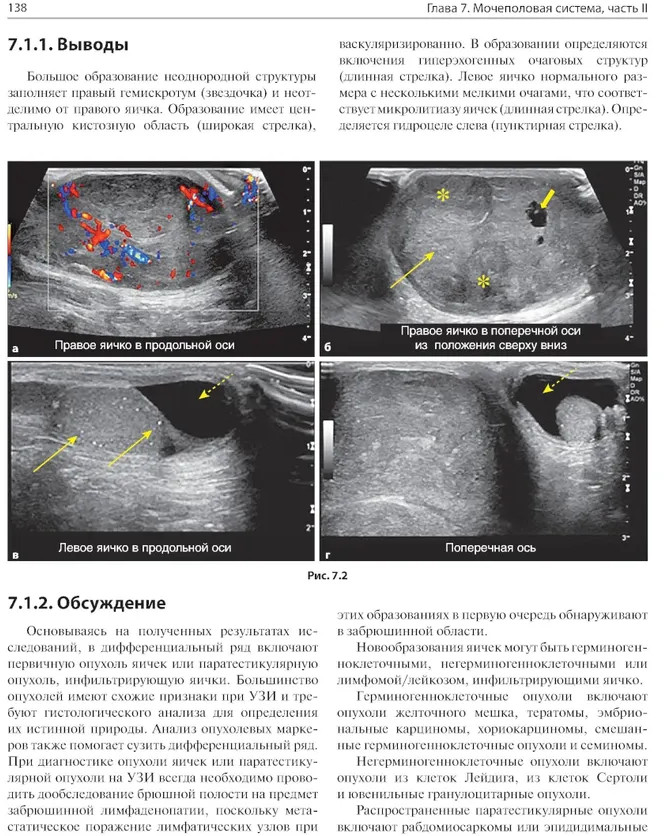

💳 Оплатить за товар можно при получении 🇰🇿 Есть бесплатная доставка по Казахстану 🎁 Копите бонусы с каждой покупки В книге рассмотрены сложные клинические радиологические случаи, охватывающие патологию центральной нервной системы, дыхательной и сердечно-сосудистой систем, желудочно-кишечного тракта, мочеполовой системы и опорно-двигательного аппарата в педиатрической практике. Случаи представлены с соответствующей историей болезни и подходящими изображениями исследований, за которыми следует обсуждение рентгенологических заключений при использовании различных методов лучевой диагностики. Также, в конце описания каждого случая выделены ключевые моменты, которые необходимо запомнить. Книга объединяет опыт врачей-рентгенологов и клинических ординаторов и представляет актуальную учебную информацию, способствующую улучшению качества оказания медицинской помощи. |